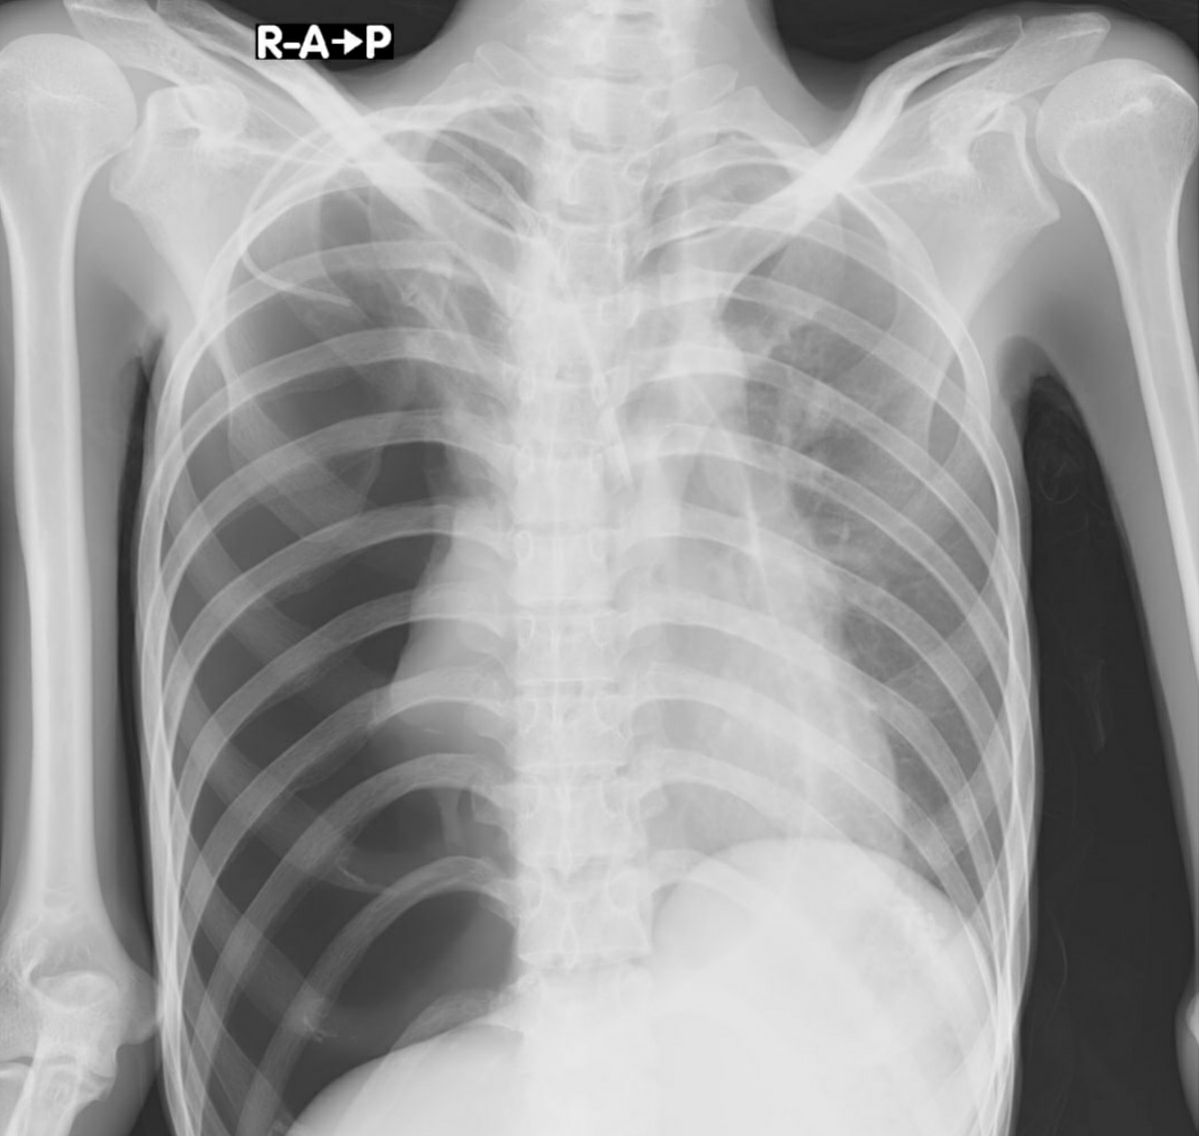

胸部肋骨骨裂是指胸部肋骨发生裂纹或骨折。这种情况对个体的影响会因程度和具体症状而异,但一般来说,胸部肋骨骨裂可能对人产生一定的影响。

胸部肋骨骨裂:影响大吗?症状及治疗